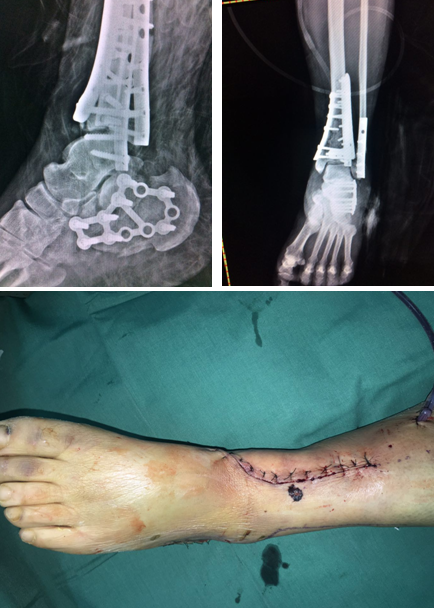

术中

4月上旬,俞光荣教授和足踝科徐明亮手术小组共同为华大姐进行了“左pilon骨折及左跟骨骨折切开复位内固定术”,手术进行了4个小时,非常成功。

“患者是双pilon骨折,双跟骨骨折,腰椎部位还多发骨折,手术不能一次做完,得分期做。一次做完的话手术时间太长容易感染,病人也承受不了。”徐明亮主任说。

目前华大姐住在足踝病区,康复效果不错,很快就要进行第二次手术了。

术后